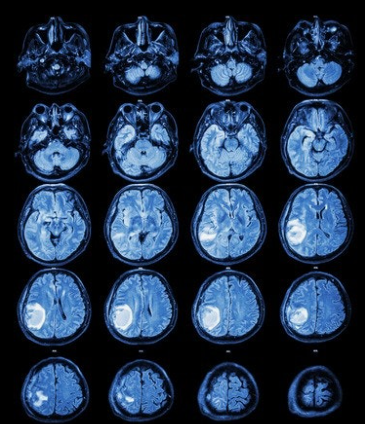

MRI(자기공명영상)는 강한 자기장과 고주파를 이용하여 인체 내부의 구조를 영상으로 보여주는 방식입니다. 방사선을 사용하지 않기 때문에 인체에 비교적 안전하며, 특히 연부조직(soft tissue)을 정밀하게 분석할 수 있는 장점이 있습니다.

MRI는 뇌의 구조적 세부사항을 고해상도로 보여줄 수 있으며, 뇌종양, 뇌졸중, 염증, 퇴행성 뇌질환 등 다양한 뇌 질환 진단에 매우 효과적입니다. 예를 들어, 초기 치매나 다발성 경화증과 같은 정밀 진단이 필요한 경우에는 MRI가 필수적입니다.

또한 기능성 MRI(fMRI)는 뇌의 활동 상태를 실시간으로 관찰할 수 있어, 뇌졸중 후 회복 경로 예측, 뇌기능 연구, 수술 전 계획 등에서 활용도가 높습니다. 하지만 MRI는 검사 시간이 20~40분으로 길고, 소음이 심하며, 체내에 금속 삽입물이 있는 환자에게는 제한적일 수 있습니다. 또한 CT에 비해 비용이 높고, 폐쇄공포증 환자에게는 부담이 될 수 있습니다.

결과적으로 MRI는 높은 정확도와 정밀함이 요구되는 진단에 적합하며, 특히 뇌질환의 조기 진단이나 진행 경과 관찰에 중요한 역할을 합니다.